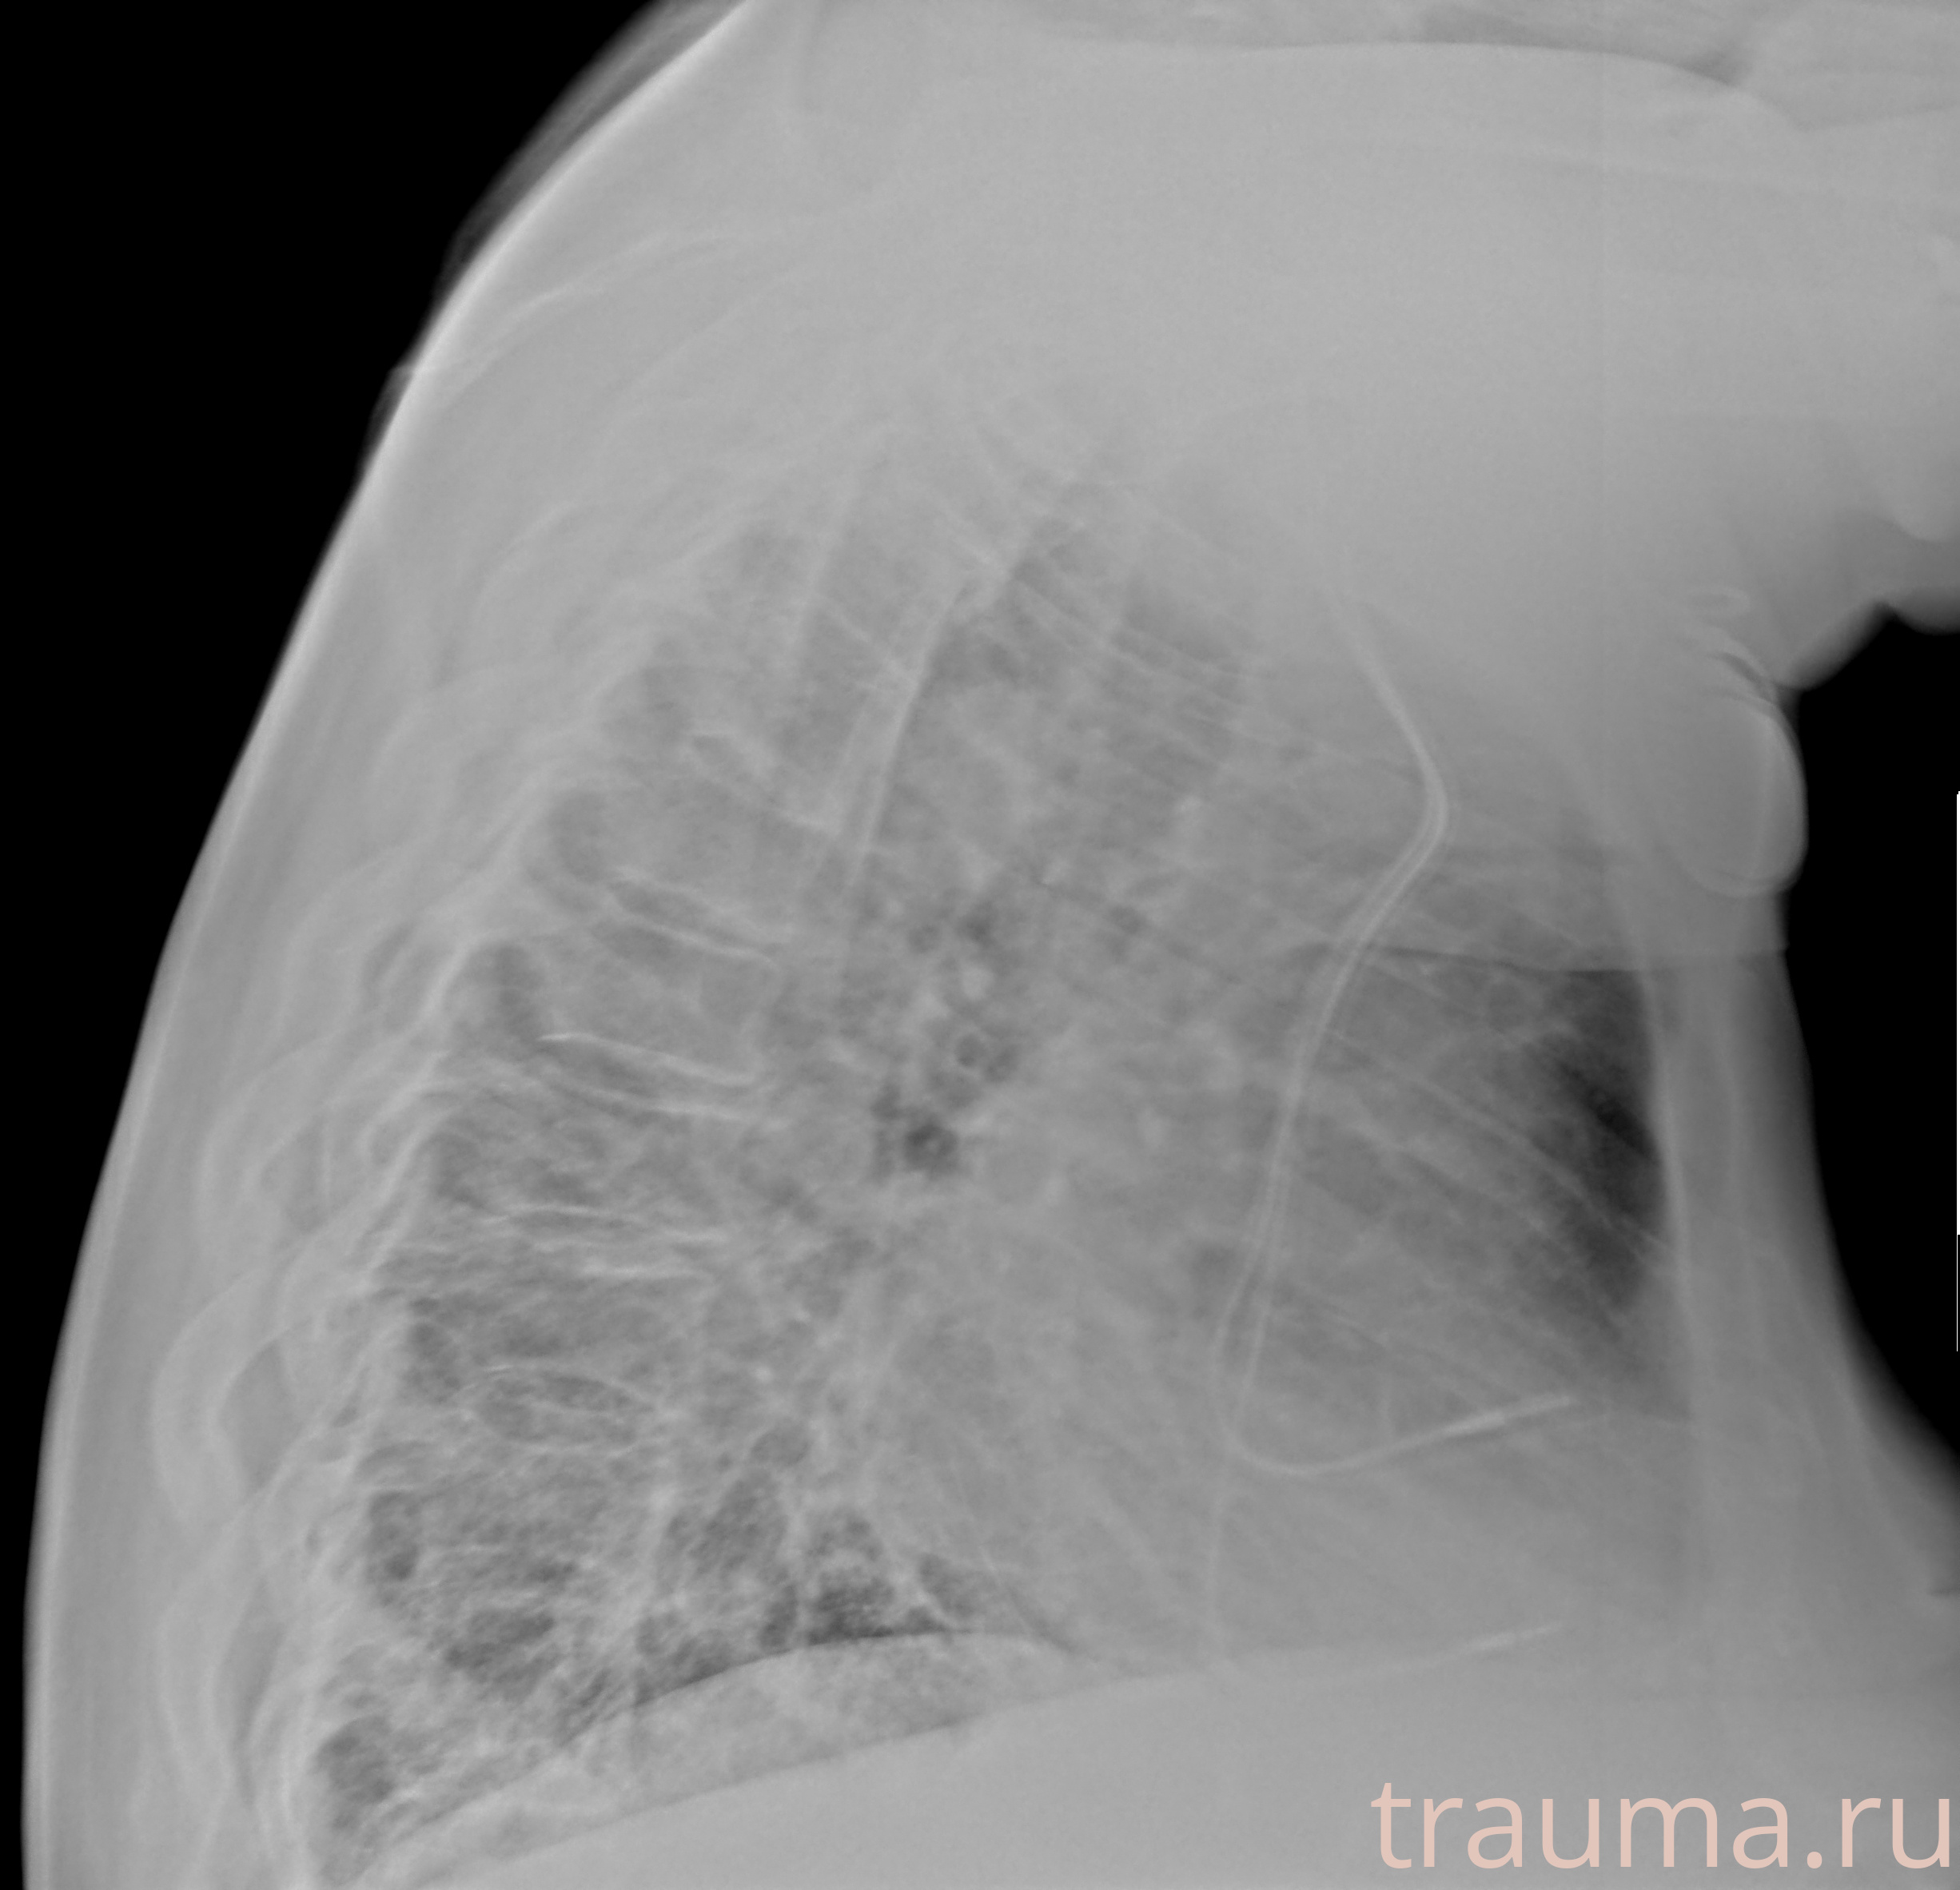

Рентген на дому: по вашему адресу приезжает врач-рентгенолог, травматолог-ортопед с мобильным рентгеновским аппаратом, проводит диагностику травмы или заболевания, делает необходимые рентгенограммы, дает рекомендации по дальнейшему лечению. Получить качественные снимки в домашних условиях возможно благодаря уникальной методике, разработанной МосРентген Центром для института  Склифосовского